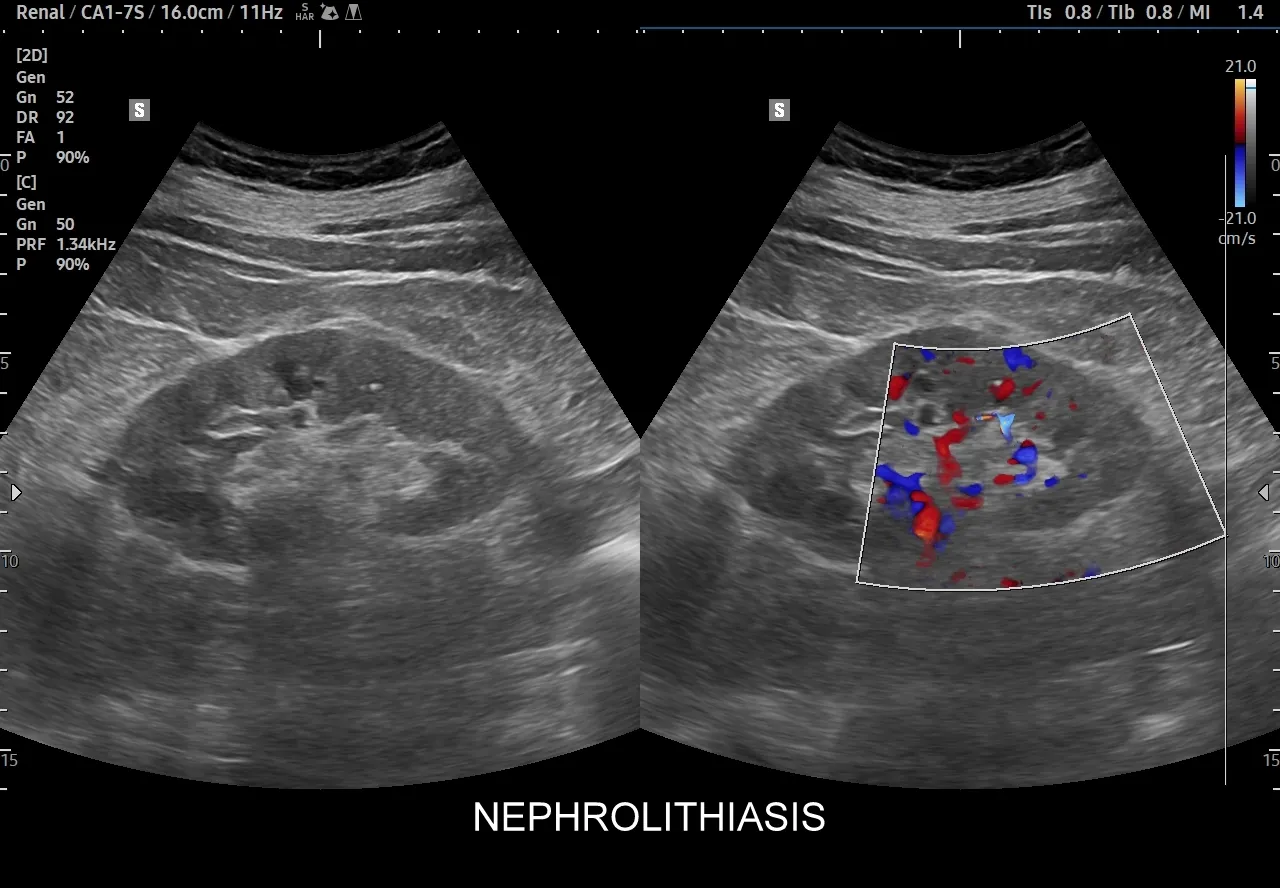

Aby "zajrzeć do środka" i dokładnie ocenić stan nerek, niezbędne są badania obrazowe. Najczęściej zaczynamy od USG układu moczowego. Jest to badanie nieinwazyjne, łatwo dostępne i pozwala szybko ocenić wielkość nerek, obecność kamieni, torbieli, wodonercza czy większych guzów. Jest to doskonałe narzędzie przesiewowe. Jeśli USG nie daje jednoznacznych odpowiedzi lub podejrzewam bardziej złożone problemy, sięgam po bardziej zaawansowane metody. Tomografia komputerowa (TK) jest niezwykle precyzyjna w wykrywaniu kamieni nerkowych, nawet tych bardzo małych, a także w ocenie guzów i zmian strukturalnych. W niektórych przypadkach, zwłaszcza gdy potrzebujemy szczegółowej oceny tkanek miękkich, naczyń krwionośnych lub gdy pacjent nie może być narażony na promieniowanie rentgenowskie (np. kobiety w ciąży), zlecany jest rezonans magnetyczny (MRI). Każde z tych badań ma swoje specyficzne zastosowanie i pomaga mi uzyskać pełny obraz sytuacji, co jest kluczowe dla postawienia trafnej diagnozy i wdrożenia skutecznego leczenia.